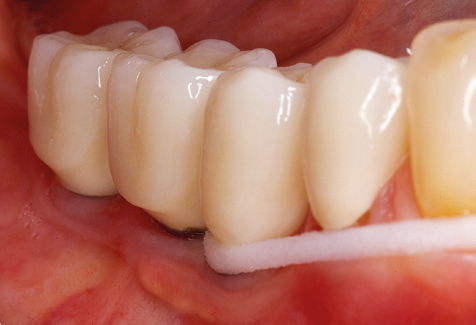

Abb. 9: Die Politur der zugänglichen Implantat­ und Zahnoberflächen erfolgt mit Polierkelchen und geeigneten Polierpasten. – Abb. 10: Die Reinstruktion zur Anwendung geeigneter Hilfsmittel bei der häuslichen Mundhygiene sollte ebenfalls Bestandteil der UPT sein. – Abb. 11a und b: Klinische Situation zwölf Jahre nach Insertion der prothetischen Versorgung. In diesem Zeitraum kam es lediglich zu einer Verblendkeramikfraktur am Zahn 47 und der Notwendigkeit einer endodontischen Behandlung am Zahn 12. Sämtliche Restaurationen sind noch in Funktion.

Für den klinischen Langzeiterfolg des parodontal kompromittierten Patienten ist die standardisierte und regelmäßige risikoadaptierte Betreuung im Rahmen der UPT der zentrale Baustein des Behandlungserfolgs. Dies gilt in besonderer Weise für Patienten, die nach erfolgreich abgeschlossener parodontaler Sanierung mit Implantaten versorgt wurden (Abb. 11a und b).